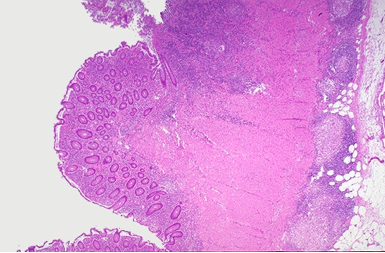

Chrons–> Crohn’s disease of the colon showing thickening of the wall, with stenosis, linear serpiginous ulcers and cobblestoning of the mucosa.

Microscopically,

Granulomas are often seen in Crohn disease,but not in ulcerative colitis